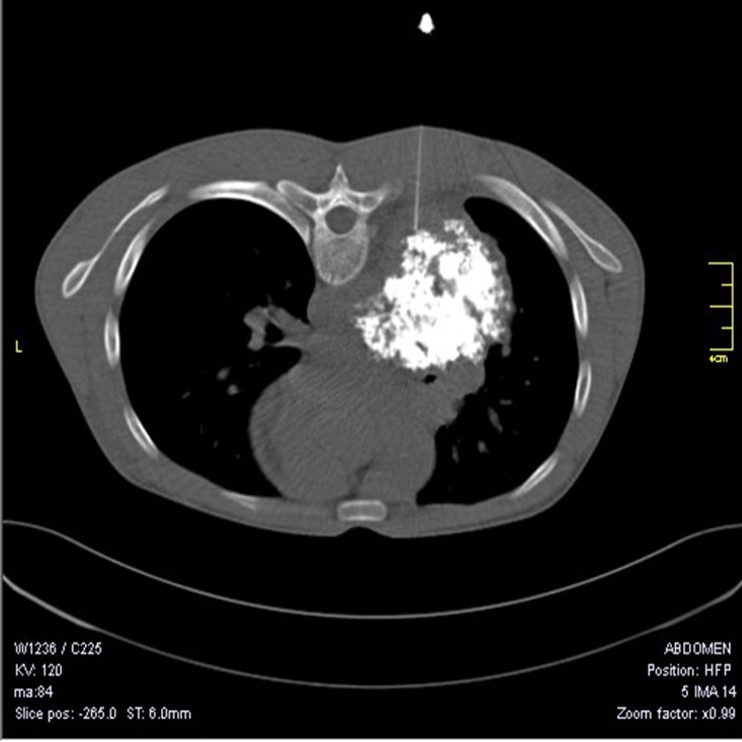

Introduction - Pulmonary hamartoma, with incidence of 0.25-0.32%, accounts for 6% of solitary pulmonary nodules. The role of radiology is limited as only 10-30% of cases show characteristic ‘popcorn’ calcification and Computed Tomography can detect approximately  50% of hamartomas. Hence cytological and/or histopathological examination is required to make a definitive diagnosis and exclude malignancy.

Objective – As pulmonary hamartoma is a rare entity detected serendipitously on radiography and requires cytological and histopathological examination for confirmation of diagnosis, we present nine cases of solitary pulmonary nodules which were diagnosed as pulmonary hamartoma.

Observations – The age of the patients ranged from 17-63 years (mean-46.3), with male to female ratio being 3.5:1. The size of the hamartoma varied from 0.4 – 1.3 cm, with mean diameter of 1 cm. Cytology showed mixture of bronchial epithelial cells, adipocytes and stromal fragments in fibromyxoid and chondroid background. Histopathology demonstrated lobules of cartilage and adipose tissue with intervening clefts lined by respiratory epithelium and mesenchymal stroma.